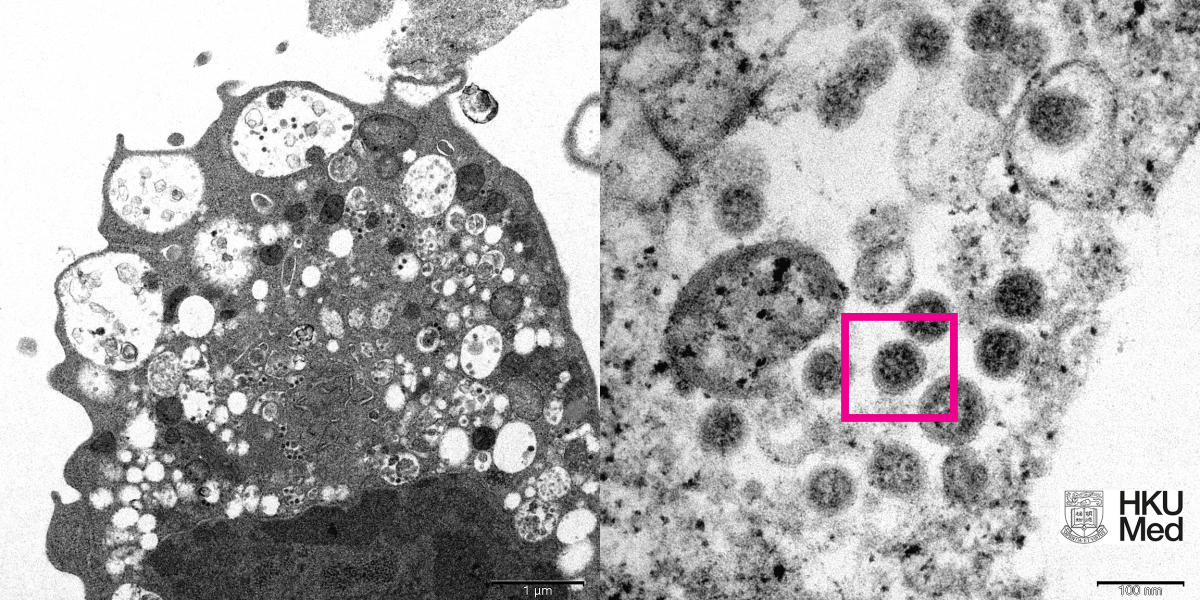

У большинства заболевших коронавирусом в Красноярском крае выявлен штамм «Омикрон». В 85% случаев. У остальных — штамм «Дельта». Это данные за последнюю неделю. Они были получены по итогам исследованных проб. О результатах сообщил в Telegram глава регионального Роспотребнадзора Дмитрий Горяев.

В Красноярском крае у 85% ковидных больных выявлен штамм «Омикрон»